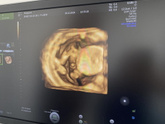

В 14 недель по узи сказали похожа на девочку, а сегодня в 18 сказали по УЗИ точно мальчик, я еще спросила точно ли? Врач подтвердила говорит точно не ошибишься в такой срок. Хотя я себя готовила к такому ответу, но в глубине души хотелось стать мамочкой … Читать далее

Мое внутреннее ощущение будто девочка, я даже нашла имя для нее ( АСИЯ) завтра пойду опять на узи перепроверять ?

Меня не отпускает мысль « Может все таки девочка » можно ошибиться в 18 недель. Как часто путают мальчика с девочкой? У кого было ???? сходить ли еще раз к другому специалисту. Я даже разговаривала с дочкой с момента двух полочек ??